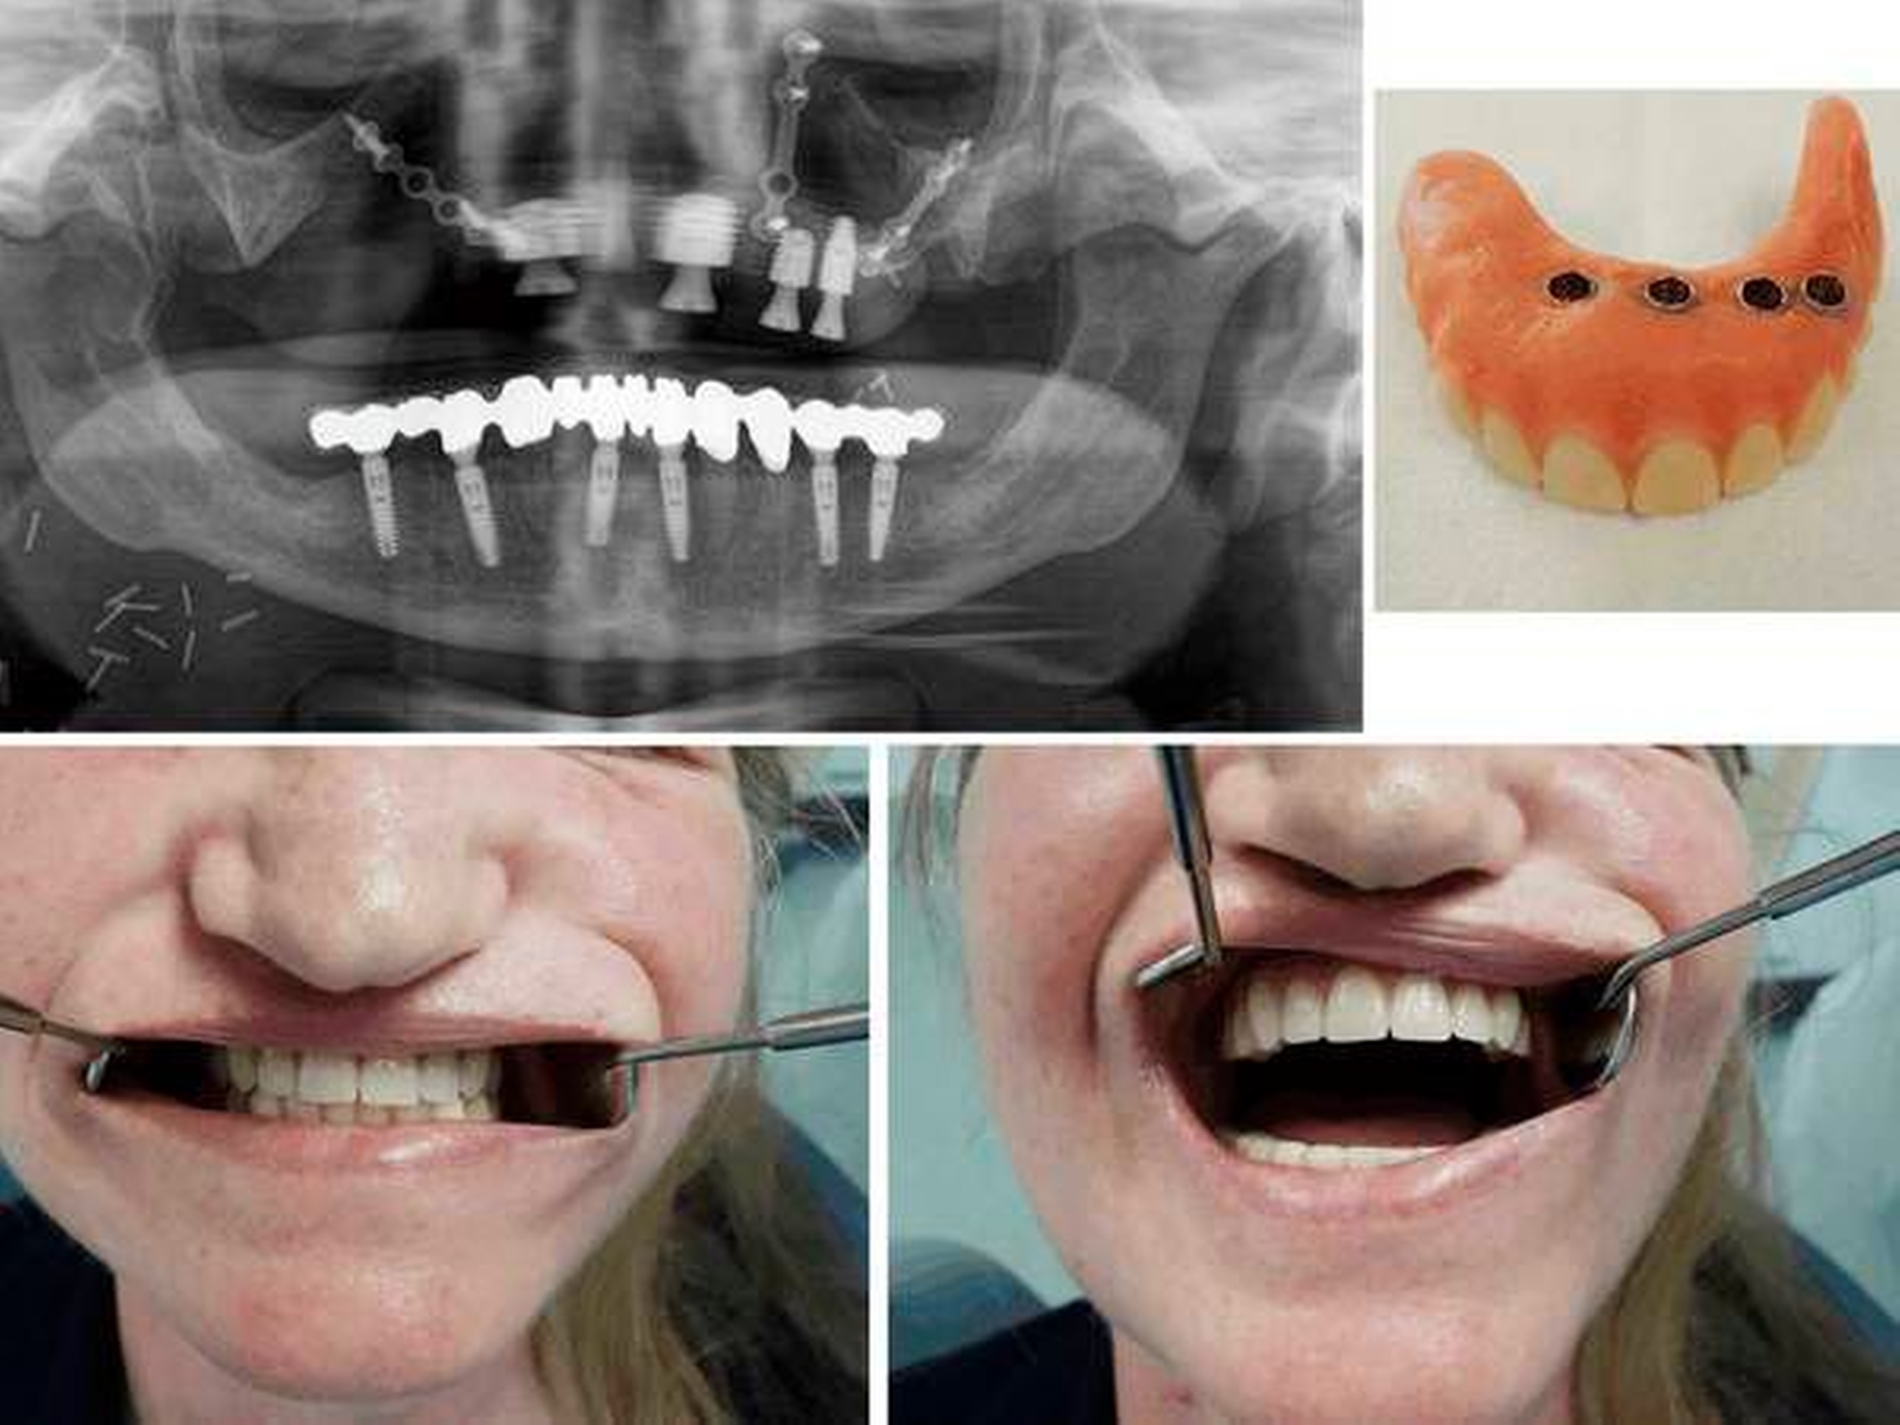

Nach einem Jahr regelmäßiger Nachuntersuchungen mit Rezidivausschluss konnten insgesamt vier Implantate in den rekonstruierten Oberkiefer eingebracht werden (Nobel Biocare, Köln). Dabei wurde eine laterale Miniplatte bei Materiallockerung entfernt. Sechs Monate später erfolgten die Freilegung der Implantate und anschließend die prothetische Versorgung der Patientin mittels eines herausnehmbaren Zahnersatzes (Abbildung 4).